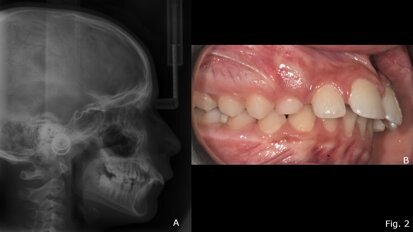

F22 Young, un dispositivo estetico funzionale per il trattamento dei pazienti in crescita con malocclusione di classe II: Case Report

La classe II scheletrica rappresenta una malocclusione molto diffusa nella popolazione e può presentarsi con un’ampia varietà di configurazioni dentali ...